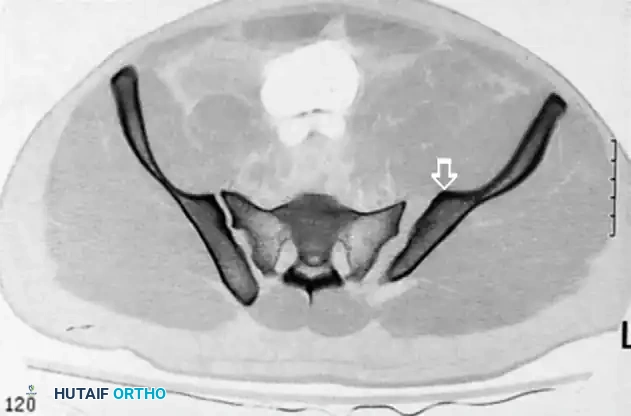

The "In-Out-In" Phenomenon

If the surgeon fails to recognize a recessed sacral ala or relies solely on inlet and outlet views without a true lateral view referencing the ICD, the screw may exit the anterior cortex of the sacrum and re-enter the vertebral body. This extraosseous trajectory directly impales or compresses the L5 nerve root.

Image

Postoperative CT scan showing a catastrophic "in-out-in" error. The cephalad anterior iliosacral screw on the patient’s left side is extraosseous, resulting in a severe left L5 nerve root injury.